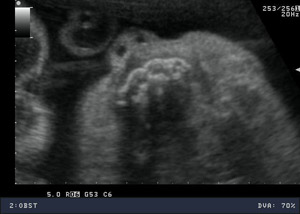

USG prenatalne 18-24 tydzień ciąży

Jest jednym z najważniejszych badań w opiece perinatalnej, polegającym na dokładnej ocenie anatomii i biometrii płodu. Wykonujemy pomiary długości kości udowej – (Femur length - FL); wymiaru dwuciemieniowego główki płodu (Biparietal diameter - BPD); obwodu główki płodu (Head circumference – HC) oraz obwodu brzuszka płodu (abdominal circumference - AC). Na podstawie tych parametrów możemy ocenić prawidłowe wzrastanie oraz masę płodu.

Jest to okres najlepszej dostępności dla oceny struktur płodu w czasie życia wewnątrzmacicznego.

W czasie badania ultrasonograficznego możemy szczegółowo ocenić struktury ośrodkowego układu nerwowego, układu moczowego, pokarmowego, kostnego, a także serca, kończyn, twarzoczaszki, łożyska i płynu owodniowego.